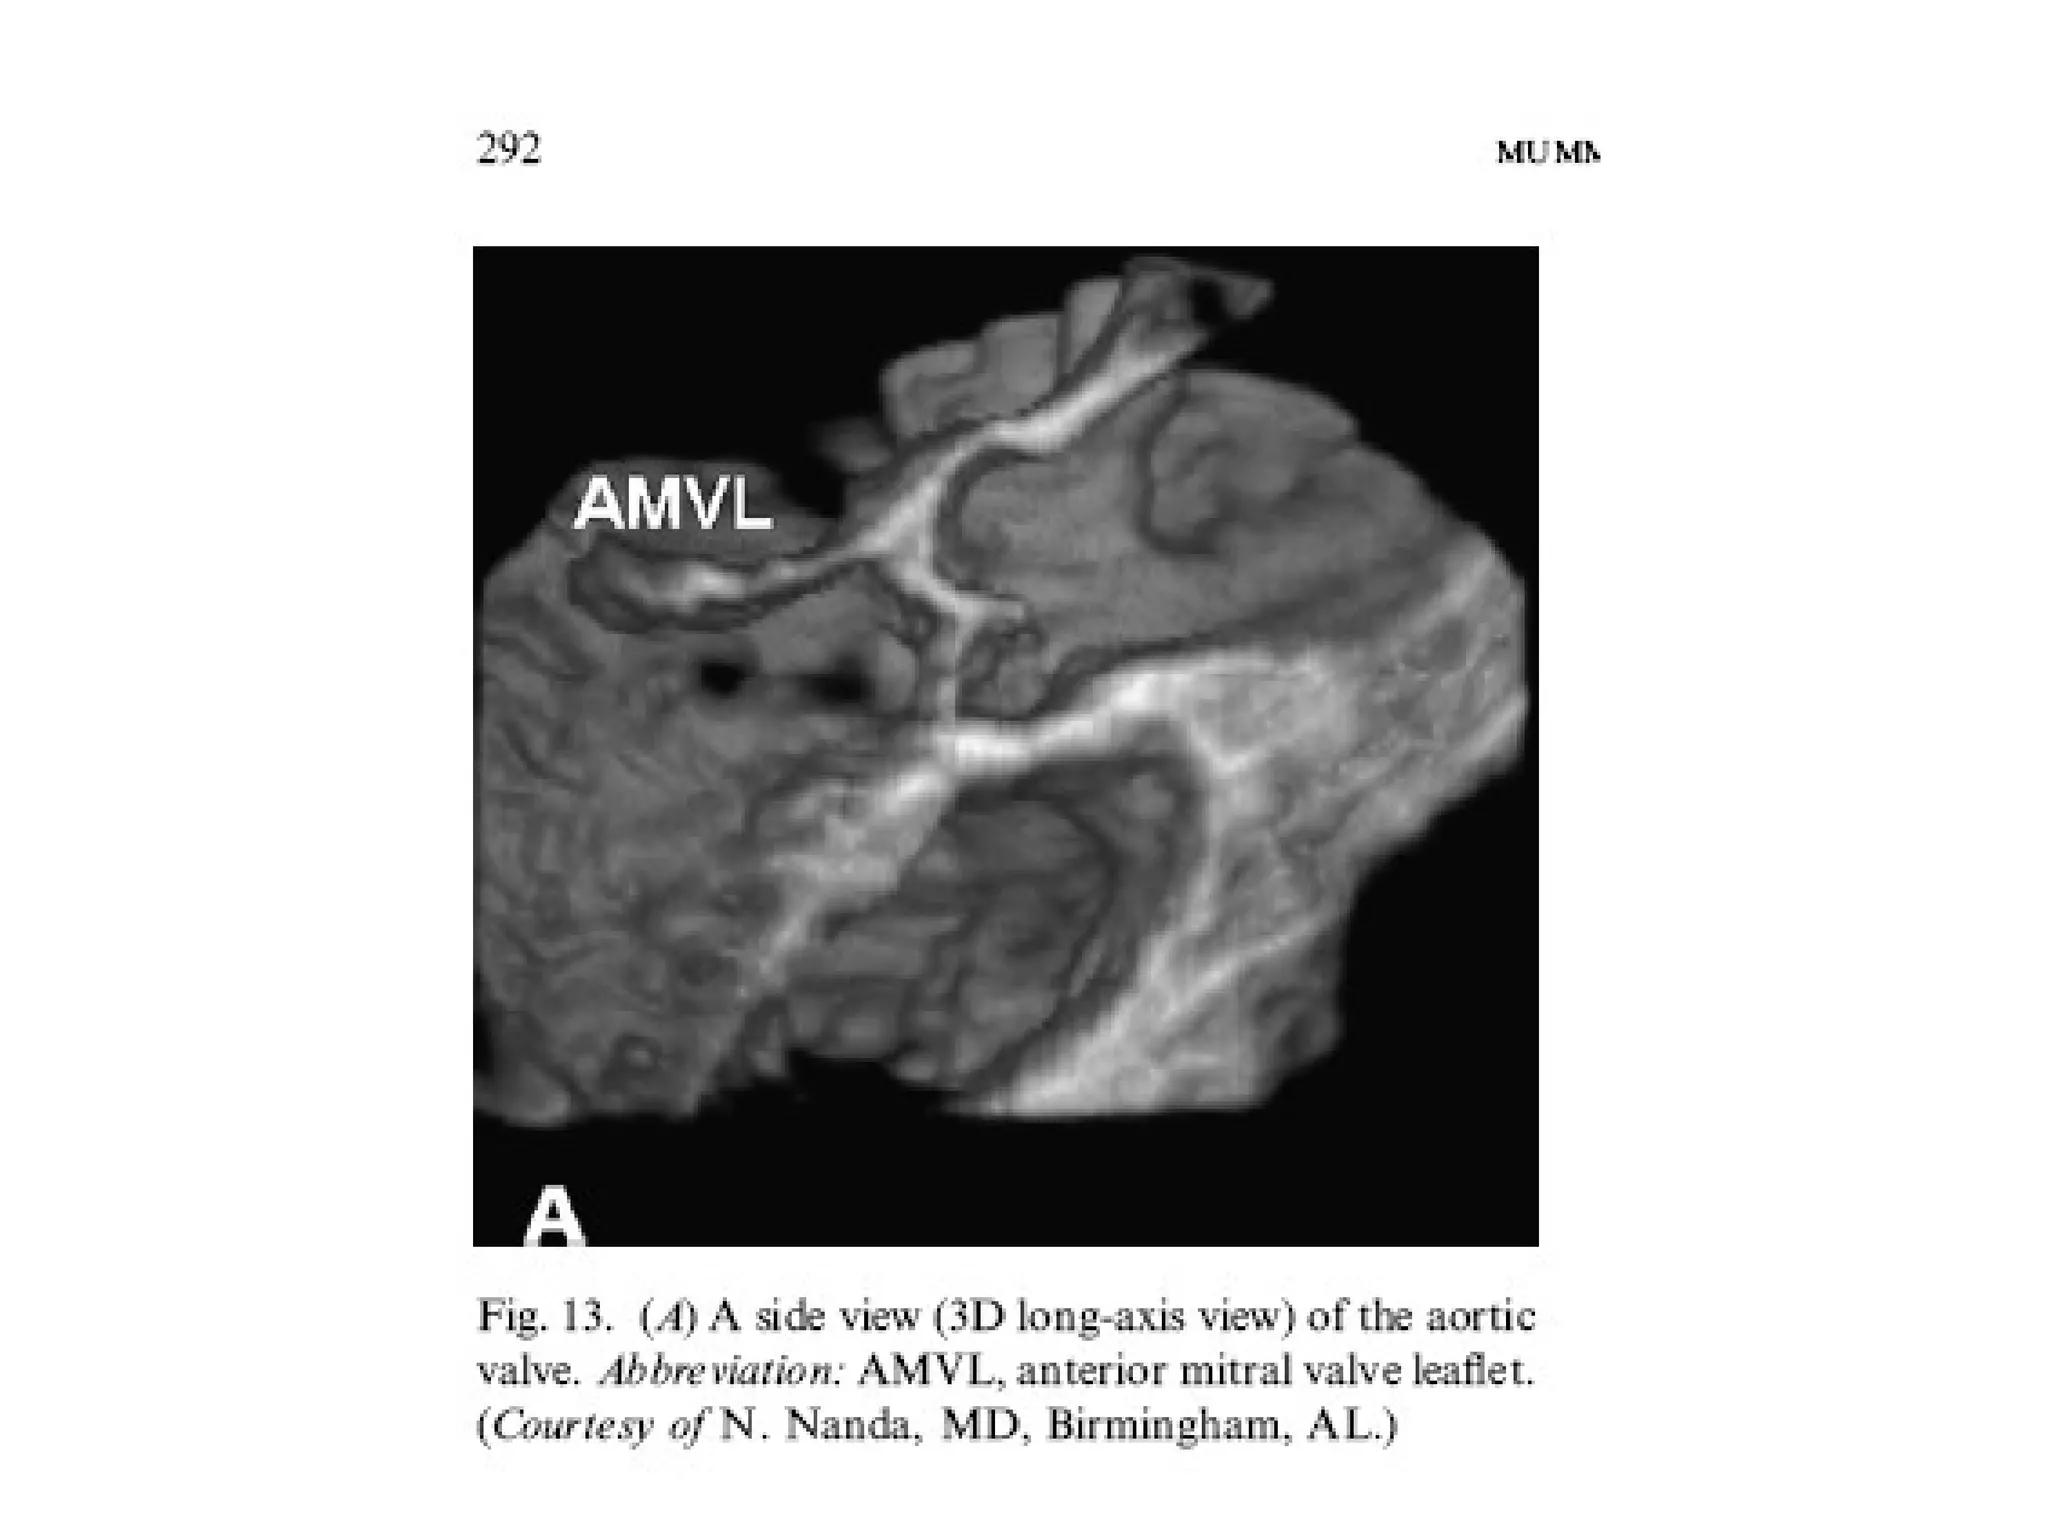

• Most studies have

been done on

mitral valve.

Understanding

about the mitral

valve annulus,

leaflet tethering,

tenting volumes

has improved with

the advent of 3 D

echocardiography